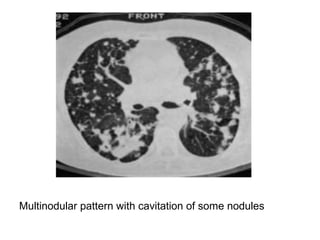

73-year-old woman with Sjogren syndrome symptoms, including dyspnea and

arthralgias, and biopsy-proven lymphoid interstitial pneumonia (LIP),

contrast-enhanced coronal reformatted image through lungs shows

numerous thin-walled cysts mostly located adjacent to blood vessels, these

perivascular cysts are identified in most patients with LIP